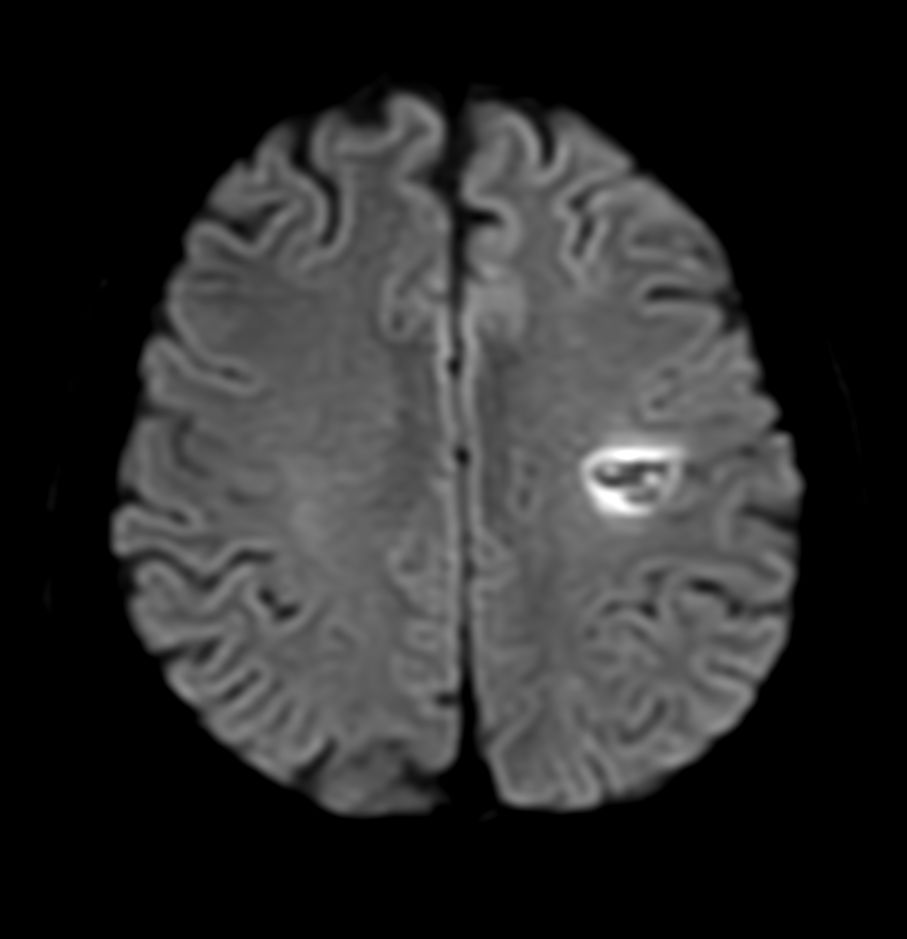

Brain small infarction

Patient with a small brain infarction. Compressed SENSE acceleration is used to speed up sequences while maintaining equal image quality. Three different diffusion methods are included; A fast 52 secs DWI EPI sequence, a high resolution DWI EPI sequence and a TSE based DWI sequence. A SWIp sequence is included offering high resolution 3D susceptibility weighted imaging to enhance contrast for deoxygenated (venous) blood or calcium deposits. 3D APT sequence is included providing contrast-free brain imaging, addressing the need for more confident diagnosis in brain neuro oncology by using the presence of endogenous cellular proteins to produce an MR signal. And a large FOV TOF MR Angiography sequence is included to check on brain vascular anatomy.

Axial DWI EPI (b1000) - High resolution